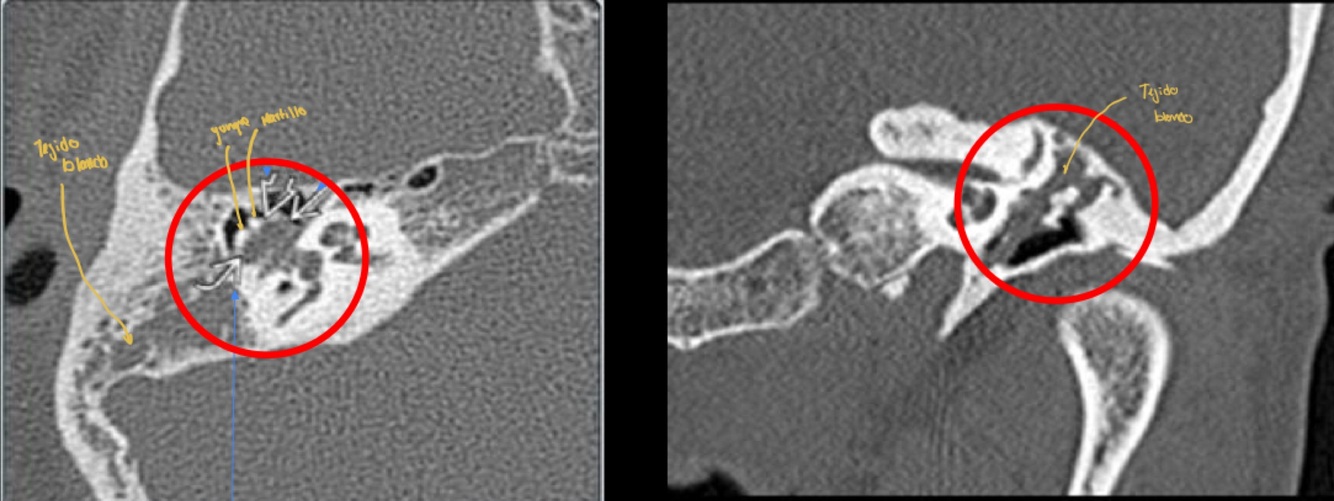

12

Q

Dx de la siguiente imagen

A

Matoiditis

Mejor estudio de imagen y clave diagnóstica de otitis media

• TC

• Masa bien definida en oído medio (densidad intermedia) + erosiones osiculares